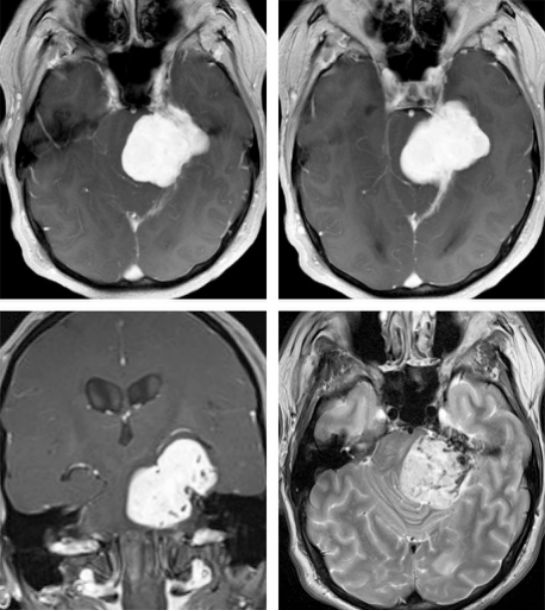

图1. 骑跨岩骨嵴的岩尖脑膜瘤。T2加权序列上大量的流空影提示该肿瘤基底部血供极为丰富(右下图。脑干受压移位明显。